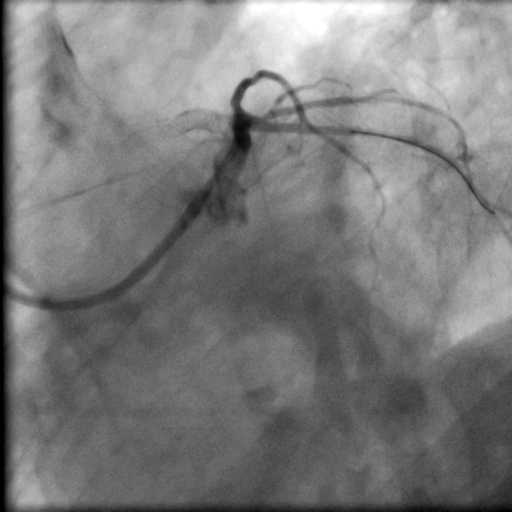

Angiogram showed satisfactory result overleft main/ramus/circumflex from prior drug coated balloon. LAD was totallyoccluded right from the ostium with an ambiguous proximal cap. Fortunately thecourse of the vessel was highlighted by the presence of calcium and stent, butthe CTO length was long. Bilateral dual injection showed faint retrograde fromright coronary artery only. J-CTO score was 3.

Bilateral injection.avi